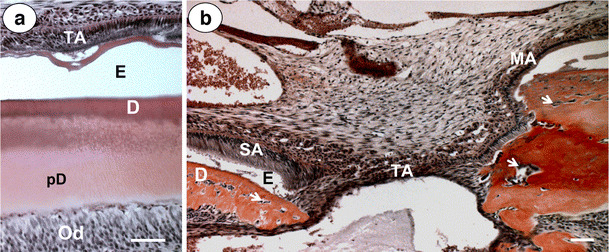

A second remarkable change after Nx was that the transitional-stage ameloblasts in the uremic incisors were always disorganized (Fig. 4a), a phenomenon not seen in the S animals. In some specimens, intact enamel (and also dentin) layers were absent under these cells (Fig. 4b). Secretory ameloblast or maturation ameloblasts were not visibly affected.

Fig. 4.

Micrographs taken from two different nephrectomized (Nx) specimens demonstrate how nephrectomy can differently affect transitional-stage ameloblasts (TA). In a, TA, although affected, were presumably able to maintain intact enamel (E) and dentin (D) layers, whereas those shown in b were not (gap area: black arrow). White arrows in b indicate cells embedded in matrix. Od odontoblasts, pd predentin, SA secretory ameloblasts. (Bars = 50 µm)

S rats exposed to F in three out of the five specimens showed changes in the transitional ameloblasts. These cells were disorganized and had formed underlying cysts. No obvious changes were noted in the secretory or maturation-stage ameloblasts, dental pulp, or odontoblasts (Fig 2b). Predentin thickness in S rats was not visibly affected by F. The F-induced changes in the incisors of the S rats were in general mild compared with those changes seen in the Nx rats. Subameloblastic cystic lesions were not observed in the S or Nx animals.

Administration of F to the uremic animals led to more severe development disturbances of the incisor, and in particular, on the transitional-stage ameloblasts, which were more disorganized compared with Nx animals (Fig. 4a). In some cases, the enamel or dentin layers were locally completely absent at these locations (Fig. 4b). F also induced the formation of more extensive cyst-like lesions under the transitional ameloblasts (Fig. 5a) found in all specimens examined. Note that a gap was observed in the root dentin in some (but not all) F+Nx animals (Fig. 5b, black double arrow). This phenomenon was also observed in some of the uremic animals not exposed to high-dose F, indicating that this is most likely not a specific F-related event.